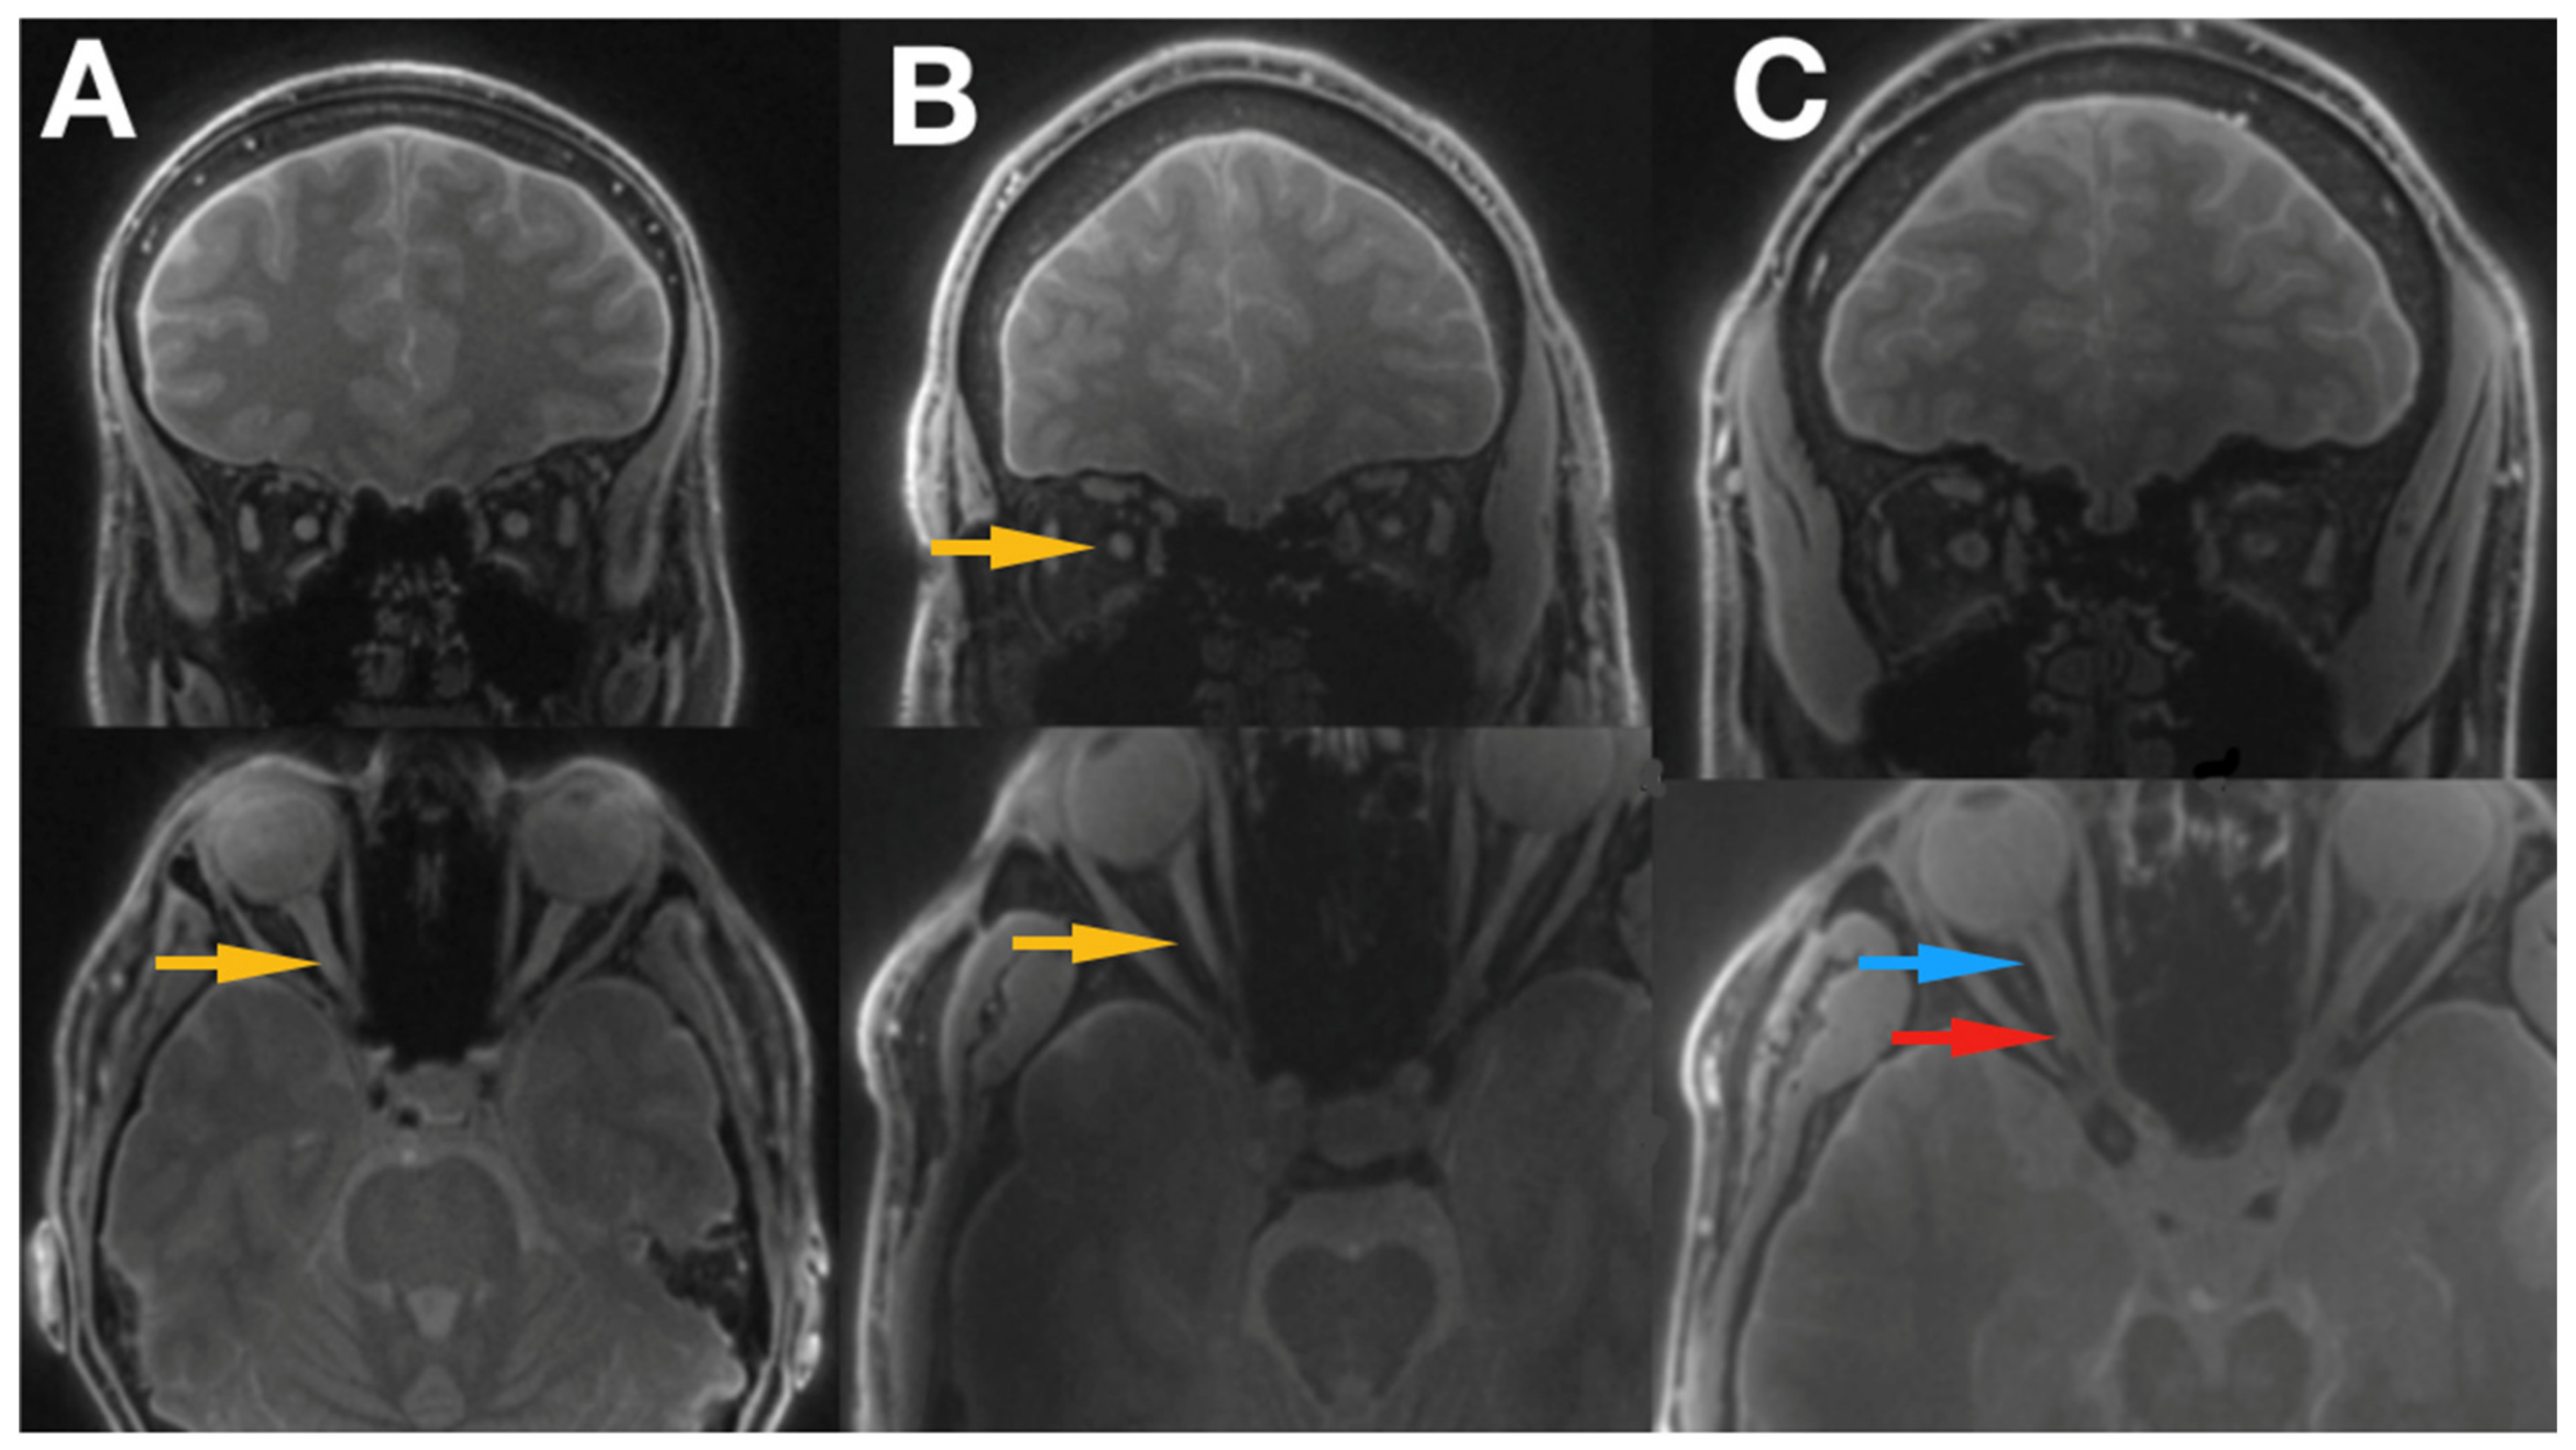

(PDF) The Evaluation of Optic Nerves Using 7 Tesla "Silent" Zero Echo Idebenone Leber's Hereditary Optic Neuropathy Leber’s hereditary optic neuropathy (lhon) is a rare mitochondrial disorder resulting in severe, bilateral vision loss. — leber’s hereditary optic neuropathy (lhon) is one of the most frequent mitochondrial disorders. — to reach a consensus on guidelines for diagnostic and clinical management including idebenone. — leber hereditary optic neuropathy (lhon) is a maternally inherited mitochondrial disease that. Idebenone Leber's Hereditary Optic Neuropathy.

JCM Free FullText The Evaluation of Optic Nerves Using 7 Tesla Idebenone Leber's Hereditary Optic Neuropathy — to reach a consensus on guidelines for diagnostic and clinical management including idebenone. — leber’s hereditary optic neuropathy (lhon) is one of the most frequent mitochondrial disorders. Leber’s hereditary optic neuropathy (lhon) is a rare mitochondrial disorder resulting in severe, bilateral vision loss. Leber hereditary optic neuropathy (lhon) leads to bilateral central vision loss. — leber. Idebenone Leber's Hereditary Optic Neuropathy.